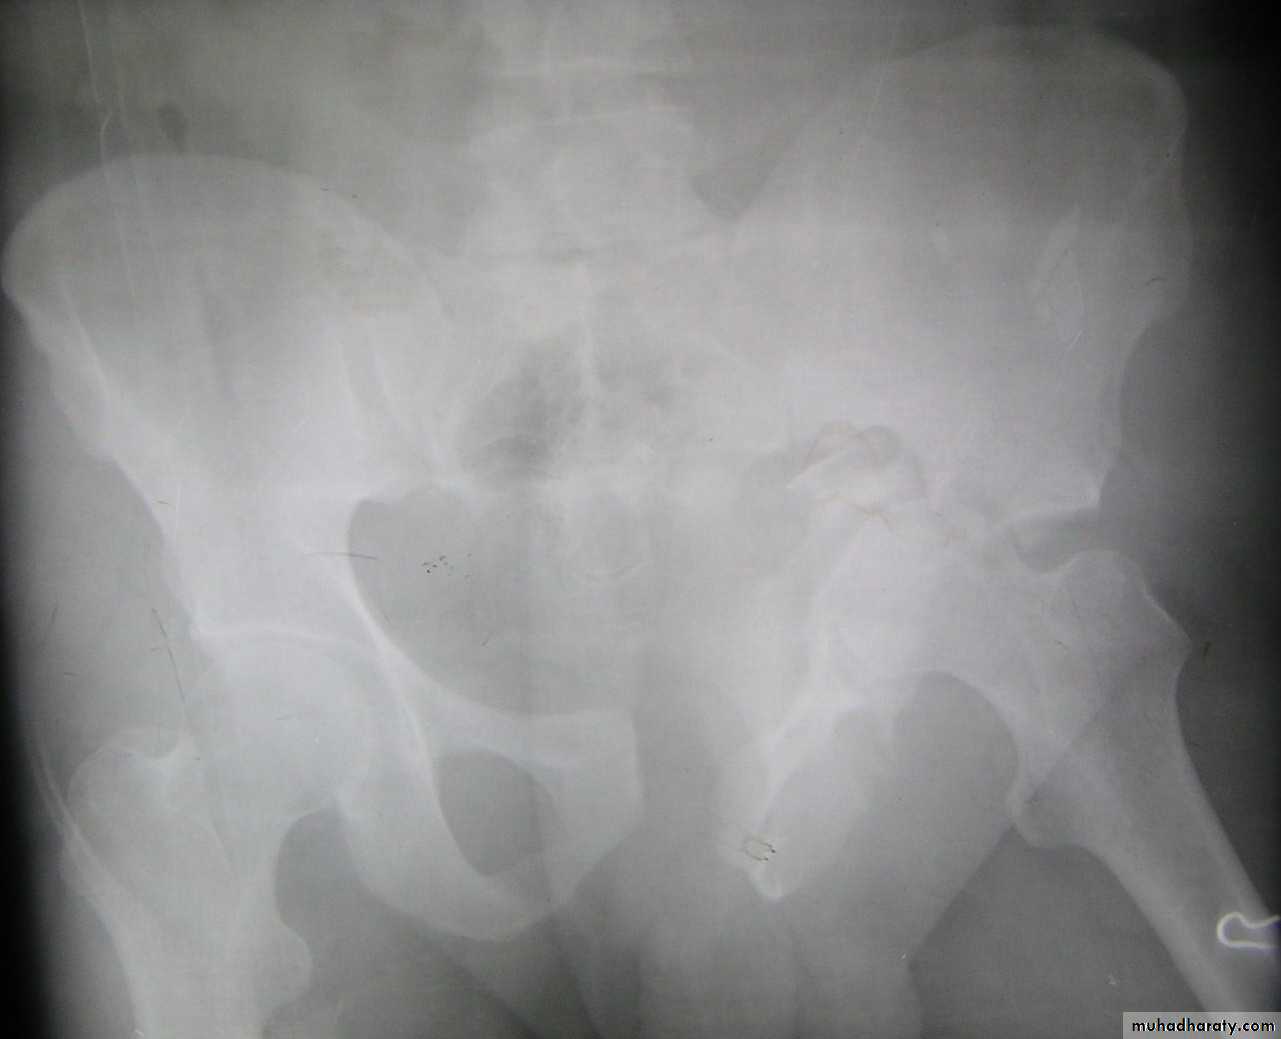

Traumatic anterior hip dislocation:Mechanism :

Road traffic accident ,miner, building laborer who is leg wide .

knees straight .

Back bent forward.

Clinically:

O\ELeg external rotation.

Abducted and slightly flexed.

Bulging head seen laterally and also feel.

Hip movement impossible.

Neurovascular examination necessary.

Radiological examination:

Hip dislocated either superior, inferior in relation to the acetabulum.Treatment: